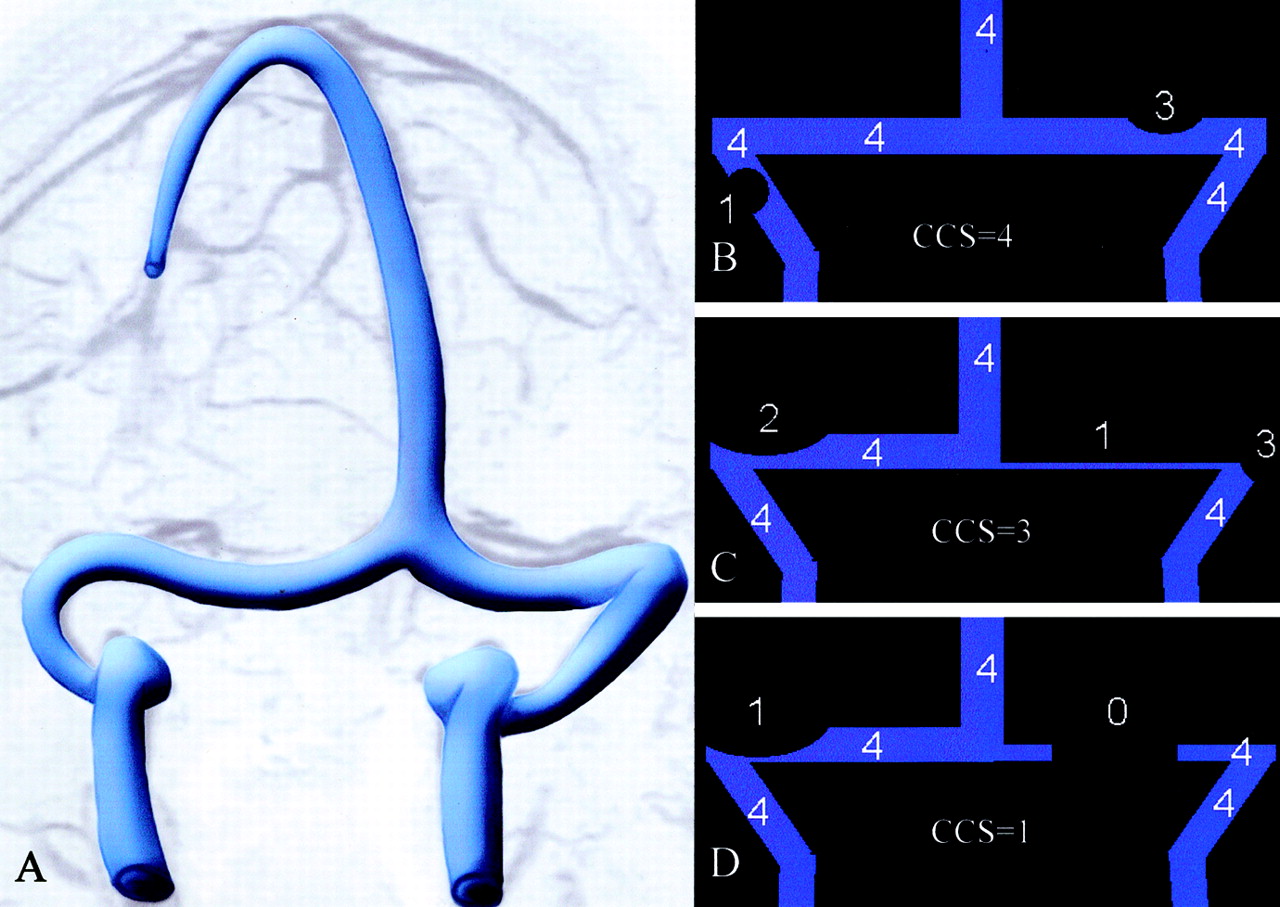

图2。系统的原理图用于分级横向的开放和乙状窦。每个左翼和右翼的年级transverse-sigmoid管道分别确定和定义的最高程度的狭窄远端从torcula遇到乙状窦并给予相应的数字从0到4。0 =不连续(gap)或再生障碍性段;1 =发育不全或严重狭窄段的管道内估计不到25%的横截面直径的远端上矢状窦腔;2 =中度狭窄的部分管道(25 - 50%),3 =轻度缩小部分(50 - 75%);和4 =无显著缩小(75 - 100%)。左翼和右翼的和合并后的管道提供得分(CCS)和通常范围从2 - 8。(A)正常情况下,每一个左翼和右翼管道将得分4的合成CCS 8,和(B, C,以及D)示意图CCS 4的例子,3,1。